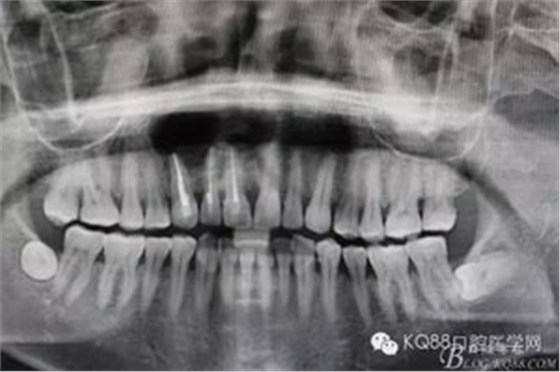

圖1.術(shù)前全景片檢查:11、12、13根尖區(qū)橢圓形陰影,邊界清楚,單囊影。初步診斷:頜骨囊腫

圖13.術(shù)后的全景片影像檢查: